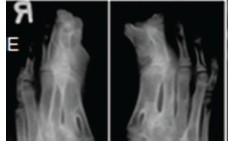

A diagnosis of Apert syndrome was made. Apert syndrome is a rare developmental condition characterized by premature cranial synostosis and resultant growth disturbances. Signs of Apert syndrome include a peaked and vertically elongated head, widespread bulging eyes, and a protuberant frontal region with an anteroposterior ridge overhanging the frontal eminence (Figure A). The palate is high, arched and occasionally cleft (Figure B). There is hypoplasia of the maxilla with relative prognatism of the mandible. Dental malocclusions with crowding and delayed dental eruption in the maxilla are common (Figure C). The facial angle is exaggerated; the nose is small and has been compared to a parrot's beak in appearance. Hypertelorism, exophthalmos and divergent strabismus are often present; sometimes with blindness. Spina bifida has been recorded in some patients. Syndactyly of the hands and feet varies greatly. Hand films in Apert syndrome showing syndactyly with fusion of three fingers in both hands and webbing (Figure D). Syndactyly of the feet in the same patient is also discernible (Figure E) Note the tall (turricephalic) skull, open metopic suture, and faint beaten-silver appearance of the calvarium. Skull base and roof of the calvarium are flattened, with a noticeable beaten-silver appearance (Figure F). The 3-D CT reconstruction of the same patient showing hypoplastic maxilla with posterior cleft (Figure G) The patient may be retarded or of normal intelligence. Apert syndrome may be associated with advanced paternal age. The cardinal radiologic features of Apert syndrome are: Brachycephalic (reduced anteroposterior dimension of the skull with increased skull width). Turricephaly (occurrence of a skull with high vertical index), beaten silver appearance of the calvarium, absence of demonstrable cranial sutures in coronal dimension in young patients, hypoplastic maxilla and syndactyly of the hands and feet. Differential Diagnosis: Crouzon's disease, Pfeifer syndrome, Carpenter syndrome and Summit syndrome.